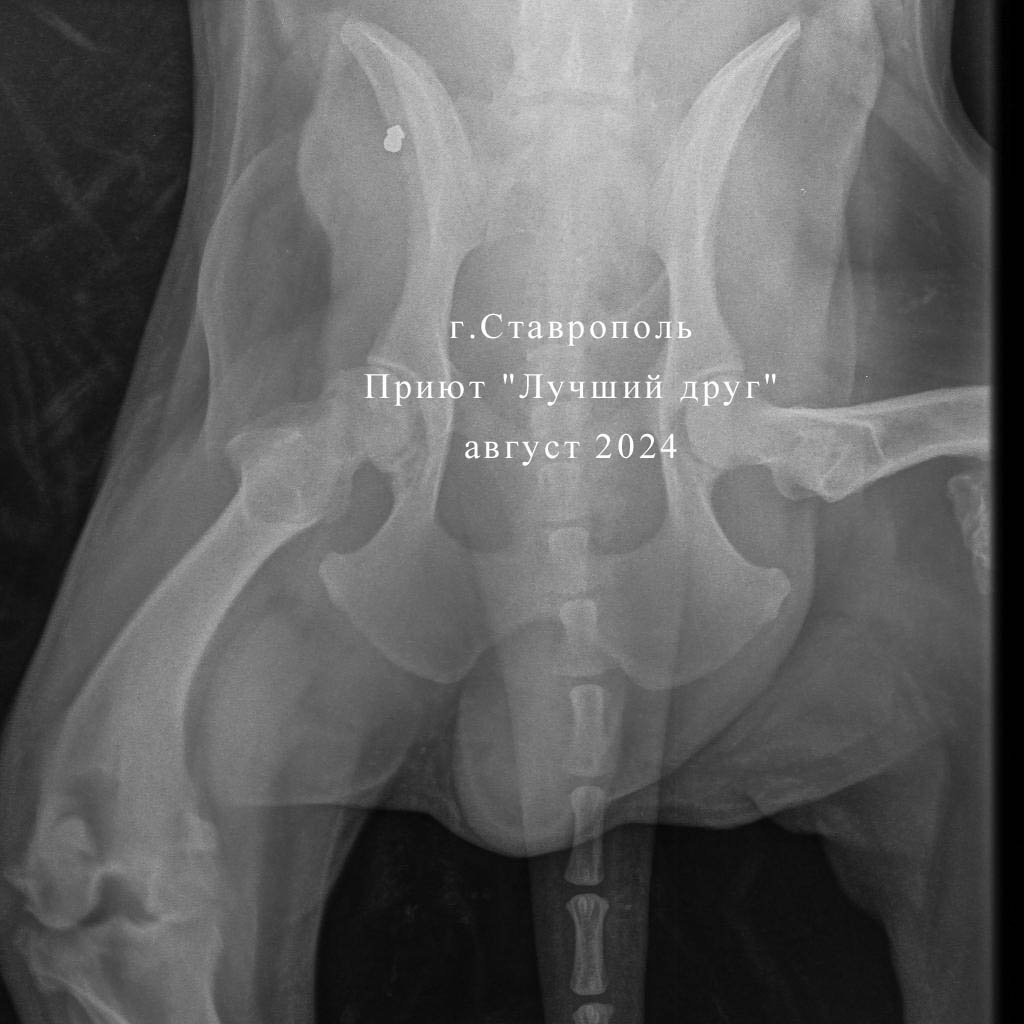

С большим трудом волонтеры привезли своенравного Мишаню в клинику, по рентгену у него перелом бедренной кости на левой тазовой конечности, сросшийся уже перелом правой задней лапы и пуля справа в подвздошной кости. Но это не так критично, как обнаруженное у пса новообразование предстательной железы. Взяли пункцию, там абсцесс, но вскрывать сейчас смысла нет. Стому не получился сделать из-за тяжелого состояния собаки. Если абсцесс вскрыть в брюшную полость, то получим по итогу спаечный процесс и перитонит. В любом случае, обширное операционное вмешательство пес не перенесет.